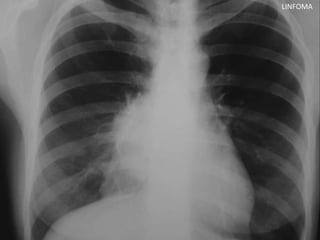

LINFOMA

LINFOMAS

• Ubicación: mediastino medio y anterior

• Clínica: poca, en general neurohumoral

• Variedades:

– Hodgkin

– No Hodgkin

• Diagnóstico: mediastinostoía, mediastinoscopía, VATS

• Tratamiento: QTX + RTX